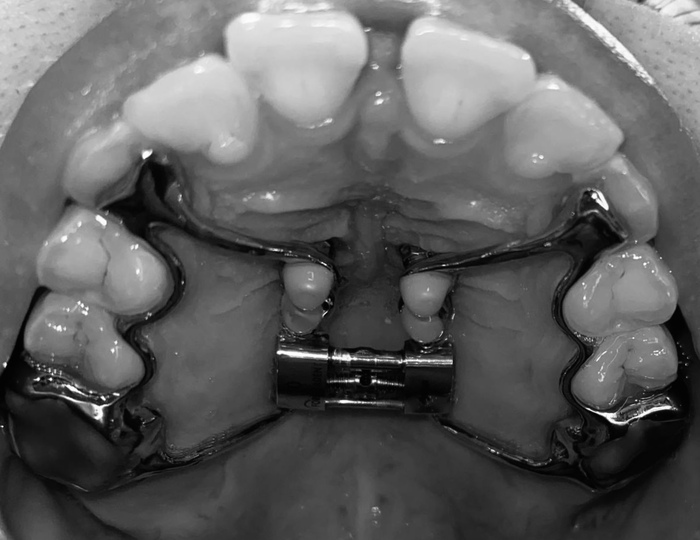

Мне удалили молочные клыки и изготовили ортодонтическую пластинку, ее еще называли «скоба», которую я исправно носила, но она почему-то мне нисколько не помогла…

И в один прекрасный день мы с родителями поехали в НН в Детскую областную больницу для дальнейшего ортодонтического лечения.

Там мне почему-то не сделали даже просто рентген, не говоря уже о КТ и забили болт на отсутствие семерок в зубном ряду, поставили «сапфировые» брекеты (которые постоянно окрашивались в желтый цвет)

Мне выровняли зубы, зафиксировали их ретейнерами и изготовили ночные каппы.